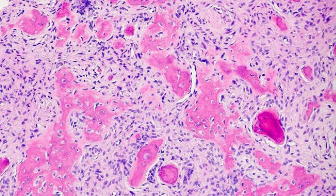

Histological image of ossifying fibroma